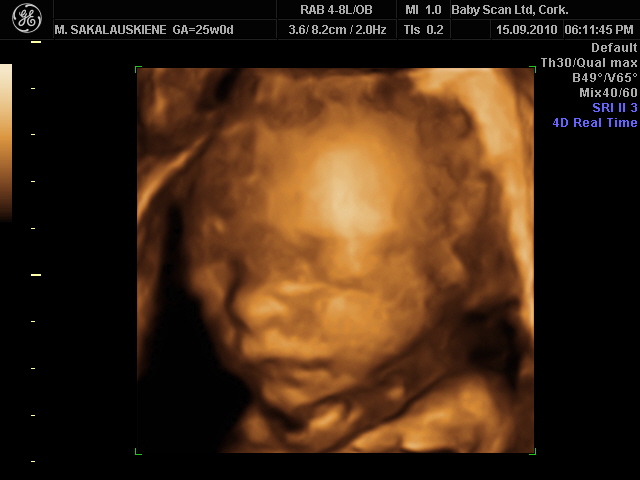

Tiriant nėščiąsias plačiausiai naudojama 2D echoskopija, tačiau populiarėja ir 4D echoskopija, leidžianti vaisių pamatyti ypač aiškiai. Skaityti

3D yra foto trimatej erdvej, 4D - video realiu laiku. Labai faina ir ispudinga, pamatai, ka tavo leliukas pilvelyje veikia ir kaip atrodo

3D yra foto trimatej erdvej, 4D - video realiu laiku. Labai faina ir ispudinga, pamatai, ka tavo leliukas pilvelyje veikia ir kaip atrodo![]()